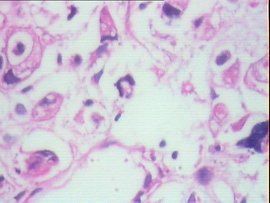

概述

胃低分化腺癌的惡性程度相對較高,發現時通常已處於中晚期,且發病迅速,預後較差。因此胃低分化腺癌的治療相對困難。早期胃低分化腺癌的治療以手術切除為主,凡臨床檢查無明顯轉移徵象,各重要臟器無嚴重器質性病變,估計全身營養狀態、免疫功能能忍受手術的胃低分化腺癌患者均應予剖腹探查的機會。早期胃低分化腺癌手術後,可根據手術切除是否完全、患者身體耐受程度的不同而輔以放化療、中醫藥治療、免疫治療等方法以防止復發。

中晚期胃低分化腺癌的治療主張多種方法綜合進行。中晚期胃低分化腺癌大多已經發生擴散轉移,難以進行手術切除,即使病人身體能夠耐受手術,也僅為姑息性切除,此時,中晚期胃低分化腺癌的治療應結合多種方法,以取長補短,發揮各自最大的優勢。胃低分化腺癌對化療不敏感,用於中晚期胃低分化腺癌的治療中,可一定程度上縮小癌腫,為手術創造機會,也可用在姑息性手術治療後,以控制病情發展,延長生存期。胃低分化腺癌對放療有一定敏感性,術前術後均可套用。胃低分化腺癌手術前放療,可縮小癌腫,提高手術切除幾率;胃低分化腺癌手術後放療,可消滅可能存在的殘留病灶以防止轉移和復發。